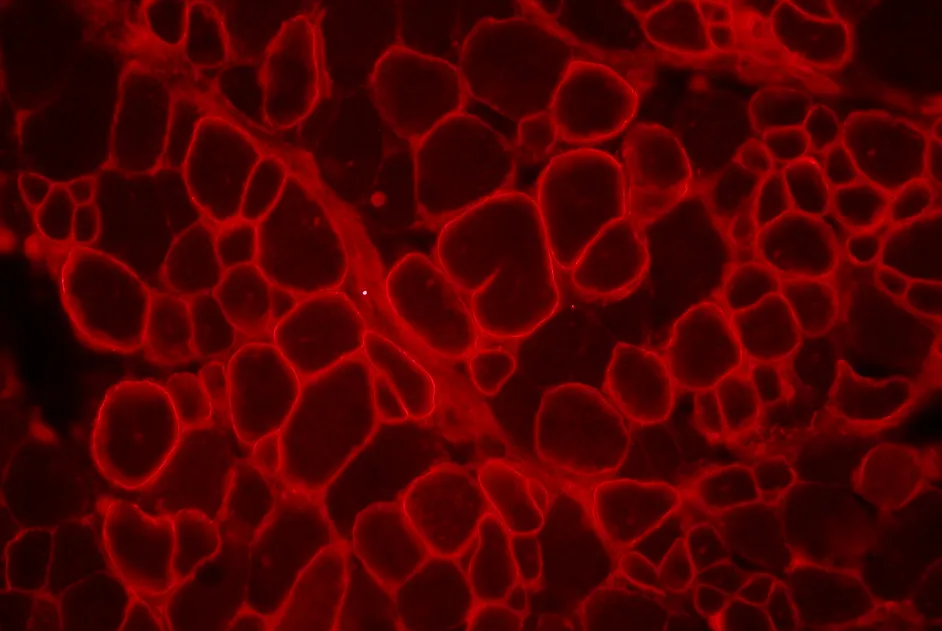

Une revue Cochrane conclut que l’entrainement aérobie est bénéfique dans la maladie de McArdle.